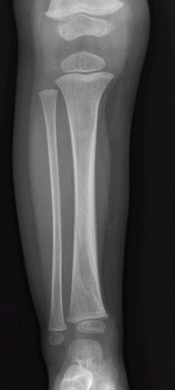

What’s the Diagnosis? Gepost op 16 september 201916 september 2019 door netwerkvsseh What’s the Diagnosis? By Dr. Michael Tom @emdaily.cooperhealth.org Dit delen: Delen op X (Opent in een nieuw venster) X Share op Facebook (Opent in een nieuw venster) Facebook Delen op LinkedIn (Opent in een nieuw venster) LinkedIn E-mail een link naar een vriend (Opent in een nieuw venster) E-mail Afdrukken (Opent in een nieuw venster) Print Vind-ik-leuk Aan het laden... Gerelateerd